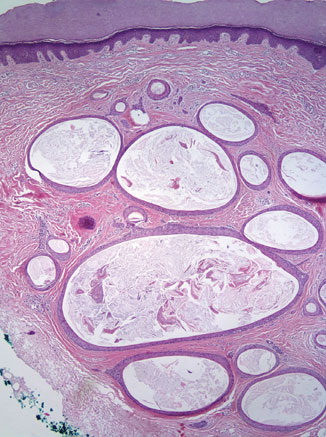

Trichofoliculoma =ورم جريبي شعري